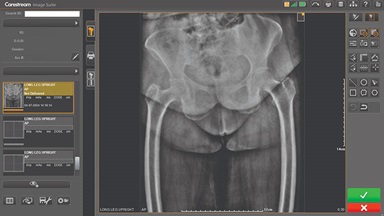

Carestream Introduces New Software Update to Boost Diagnostic Accuracy

Carestream today announced the latest update to its Image Suite V4 Software, MR 11: a series of enhancements to help improve customer confidence and increase diagnostic accuracy [...]